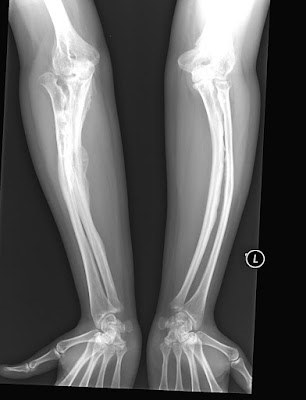

Osteogenesis imperfecta, commonly called brittle bone disease, is a genetic disorder. It is an autosomal dominant disease, which means a person can get if only one of their parents has the abnormal gene. OI affects the part of the bones called the collagen rod, which provides bone strength. ... Read Article

Osteogenesis imperfecta, commonly called brittle bone disease, is a disease that causes a defect in the production of a protein called collagen. ... Read Article

Osteogenesis imperfecta (OI), also known as brittle bone disease or Lobstein syndrome, [1] is a congenital bone disorder characterized by brittle bones that are prone to fracture. ... Read Article

Brittle Bone Disease/ Osteogenesis Imperfecta Osteogenesis Imperfecta (OI) is a disorder which causes the bones to break easily. It is also called ... Doc Retrieval